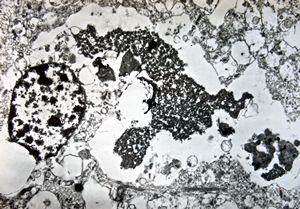

M, | cerebral cortex - malaric pigment